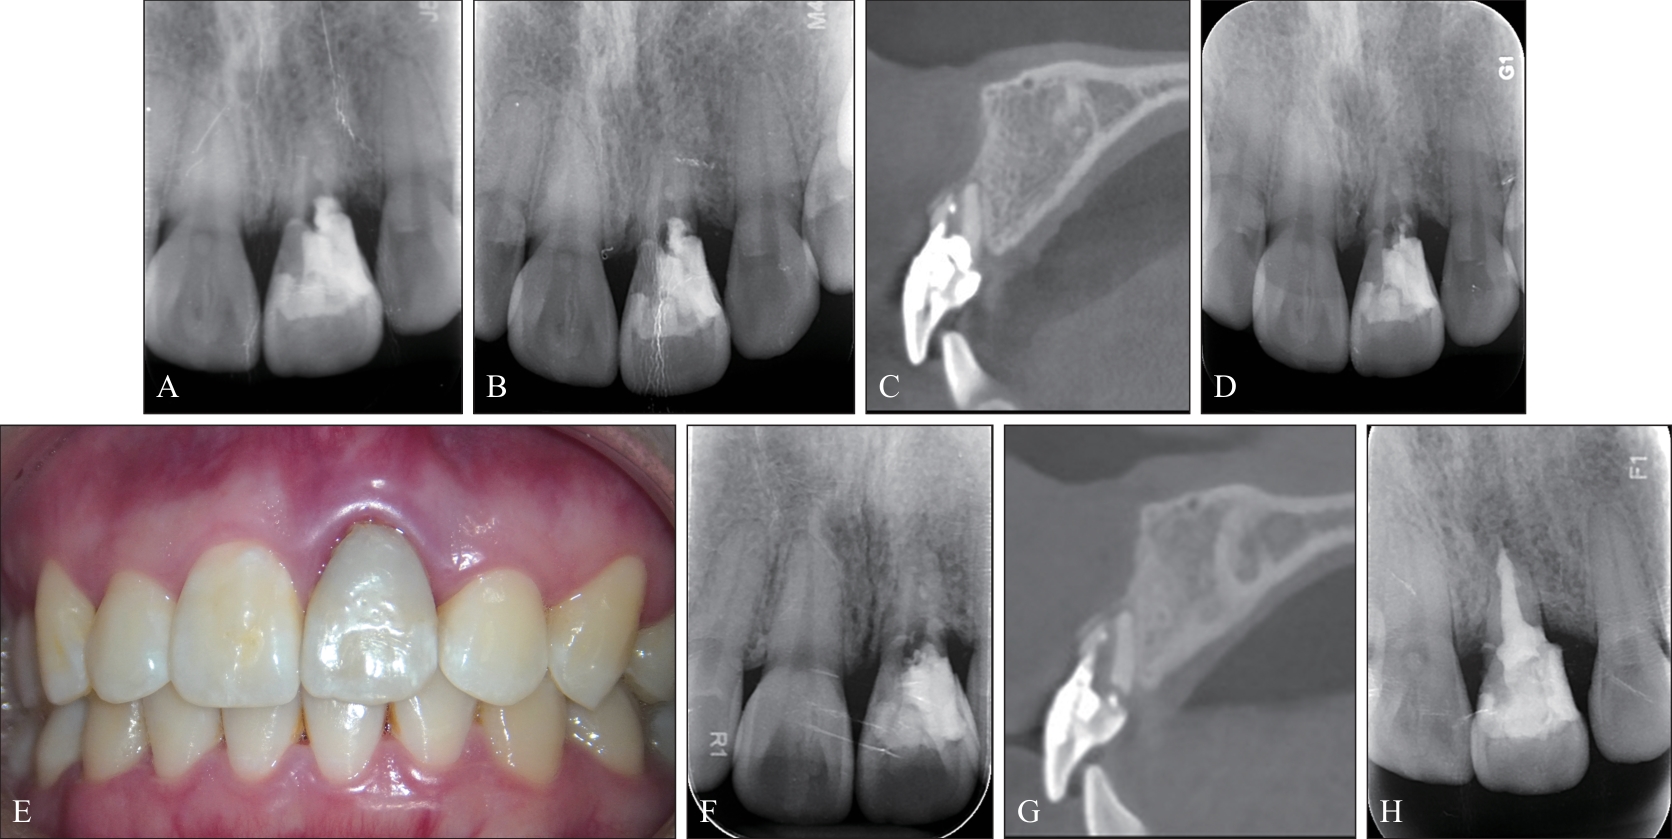

Patel S, Foschi F, Mannocci F, et al. External cervical resorption: a three-dimensional classification[J]. Int Endod J, 2018, 51(2): 206-214

Patel S, Krastl G, Weiger R, et al. ESE position statement on root resorption[J]. Int Endod J, 2023, 56(7): 792-801.

Patel S, Foschi F, Condon R, et al. External cervical resorption: part 2—management[J]. Int Endod J, 2018, 51(11): 1224-1238.